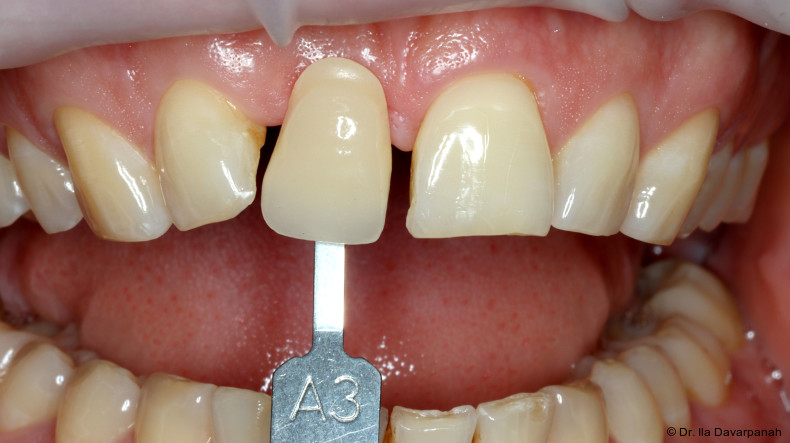

Neben patientenbezogenen und chirurgischen Faktoren spielt dabei auch das Implantatdesign eine wesentliche Rolle. Die vorliegende Falldokumentation zeigt eine Sofortimplantation Regio 11 mit digitaler Planung anhand von DICOM- und STL-Daten. Die präoperative Planung erfolgte softwaregestützt, die Implantatposition wurde prothetisch orientiert festgelegt. Klinisch und radiologisch lagen günstige Ausgangsbedingungen für eine Sofortimplantation mit Sofortversorgung vor.

Zur Erreichung einer hohen Primärstabilität wurde ein Implantat mit aggressivem Gewinde bei einem Außendurchmesser von 3,5 mm und einem Kerndurchmesser von ca. 2,8 mm eingesetzt. Ergänzend erfolgte eine unterpräparierte Bohrung. Solche Kombinationen aus Gewindedesign, Implantatgeometrie und Bohrprotokoll sind in der klinischen Praxis etabliert, erfordern jedoch eine sorgfältige Risikoabschätzung hinsichtlich der mechanischen Belastung des Implantatkörpers.